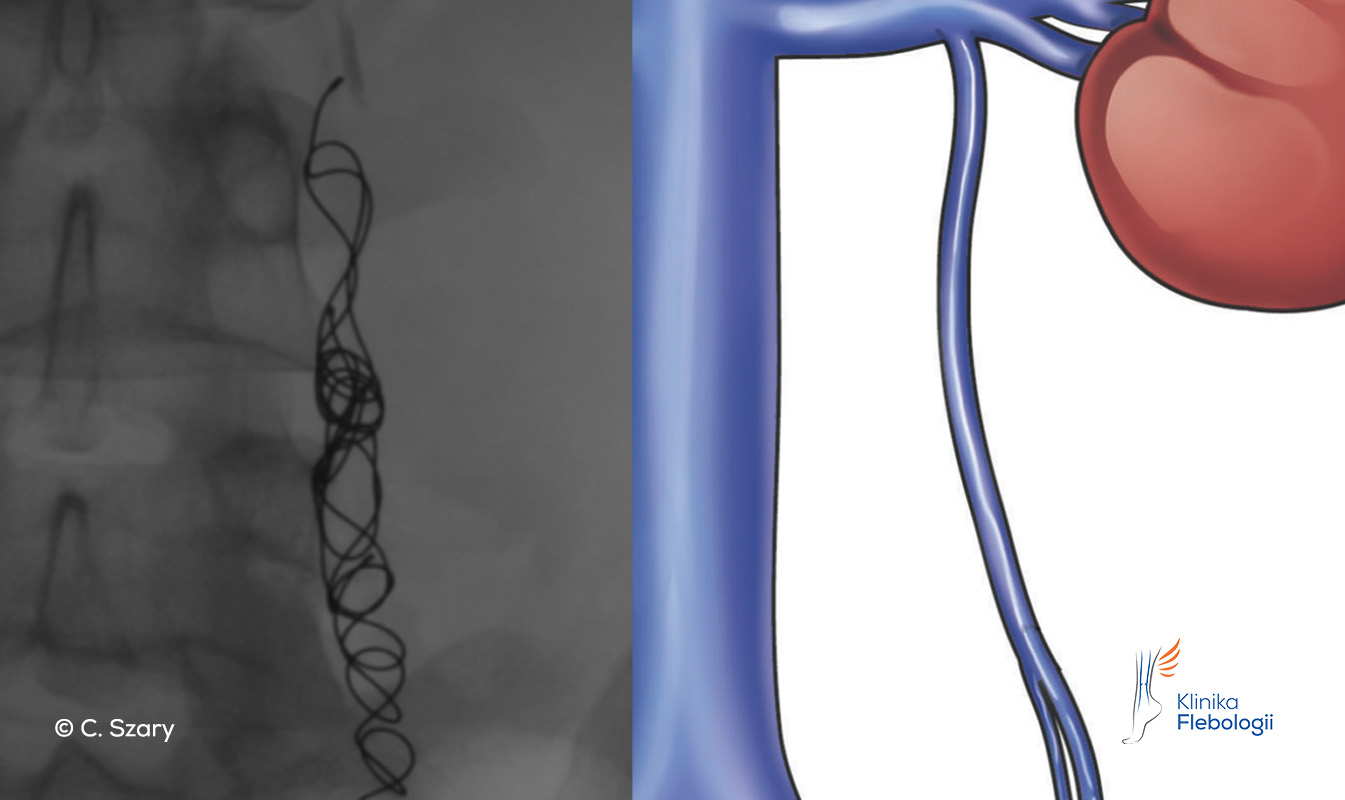

Stan po embolizacji niewydolnej żyły jajnikowej lewej przy użyciu spiral embolizacyjnych

Spirale embolizacyjne stosowane do zamykania niewydolnych żył

Przy zabiegach embolizacji żylnych lekarze zespołu Kliniki Flebologii wykorzystują najczęściej spienione sklerozanty (zapewniają wysoki poziom bezpieczeństwa), polimeryzujący klej tkankowy oraz nowoczesne spirale (tzw. coile), które są kompatybilne z wysokoteslowymi systemami rezonansowymi (zatwierdzone do pola o sile 3T).